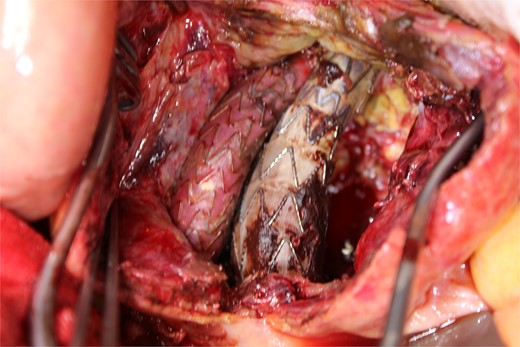

Contrast-enhanced CT revealed an AAA measuring 118 × 107 mm and left retroperitoneal hematoma. One pair of lumbar arteries was enhanced only in the delayed phase (red arrows). Intraoperatively, pulsatile bleeding was observed from the left one of this pair.

This time, he was brought to the emergency department with a chief complaint of abdominal pain. His medical history includes Stage 4–5 chronic kidney disease (CKD), with an estimated glomerular filtration rate (eGFR) of approximately 15 mL/min/1.73 m2, secondary to nephrosclerosis and diabetic nephropathy, as well as persistent atrial fibrillation, which was treated with warfarin. Upon admission, laboratory results revealed a hemoglobin level of 6.2 g/dl and a prothrombin time—international normalized ratio (PT-INR) of 6.05. Contrast-enhanced CT demonstrated an AAA measuring 118 × 107 mm, enlarged from 98 × 94 mm 2 months prior, and left retroperitoneal hematoma. IMA and one pair of lumbar arteries were enhanced only in the delayed phase, but blood flow into the aneurysm was not clearly observed (Fig. 1). Given that the landing zones and overlaps of the stent grafts were satisfactory (Fig. 2) and that no type I or type III endoleaks were identified, a ruptured AAA due to TIIEL from the lumbar artery or IMA was highly suspected. We administered 3000 IU/kg of lyophilized human prothrombin complex concentrate in response to the significant prolongation of PT-INR and proceeded with open surgery for ligation of the feeding artery and aneurysmorrhaphy. Intraoperatively, no pulsation was found on the aneurysm. Incision of the aneurysm revealed a large amount of thrombus, which was removed, and then pulsatile bleeding was identified from a lumbar artery (Fig. 3), the ostium of which was sutured from within the aneurysm. This was consistent with the left lumbar artery of the pair enhanced on the preoperative CT and was suspected to be responsible for the rupture. Oozing was also noted from several other lumbar arteries, which were similarly sutured closed. No leak was observed from the proximal or distal ends, nor from the junctions of the stent grafts, and no damage to the stent grafts was observed (Fig. 4). Following this, aneurysmorrhaphy was performed, and the abdomen was closed. The postoperative course was uneventful. A plain CT on postoperative day (POD) 14 showed a reduction in the aneurysm size with no apparent leaks (Fig. 5). The patient was discharged home on POD 24. Although the preoperative eGFR was 8.8 ml/min/1.73 m2, no postoperative deterioration was observed. It gradually improved back to baseline, and dialysis was not required during the follow-up period.

A photo taken from the cranial side of the patient. A jet of bleeding was identified from a lumbar artery.